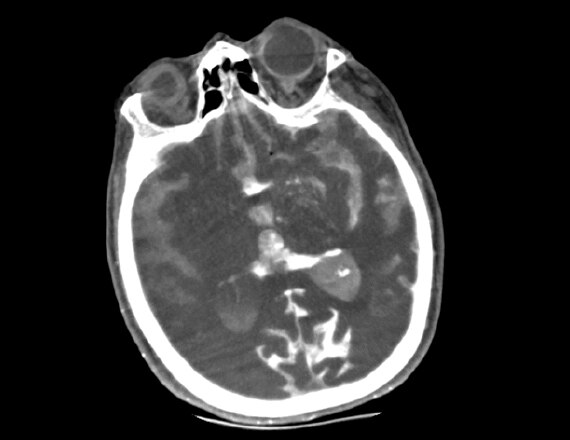

L'accident ischémique cérébral aigu est une maladie complexe et le succès de son traitement endovasculaire repose sur la capacité globale d'intégrer rapidement plusieurs éléments d'information.4 Entreprendre une thrombolyse intraveineuse (IV-tPA) si l'AVC ischémique dure moins de 5 heures. Débuter la procédure de thrombectomie mécanique dans les 6 heures qui suivent le début de l'accident vasculaire au niveau d'un gros vaisseau (zone de l'artère cérébrale moyenne). Des interventions réalisées dans les plus brefs délais avec une imagerie précise permettent d'atteindre rapidement les lésions et de prodiguer des soins de meilleure qualité aux patients.

IGS 630 avec Advantage Workstation

Interventions rapides pour favoriser la détection des hémorragies dans la salle. Pour en savoir plus

Innova CT HD

Permet de détecter rapidement les hémorragies intracrâniennes dans la salle d'intervention. Pour en savoir plus